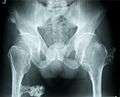

multiple osteochondromas at the pelvis